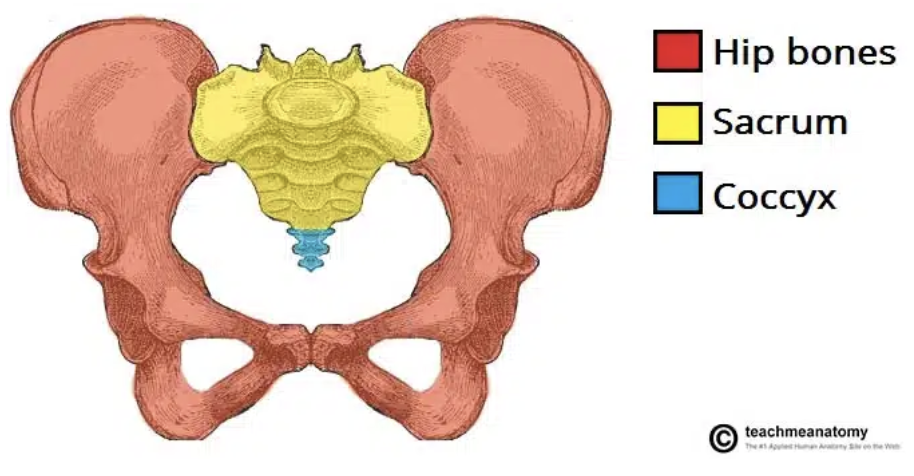

how many bones are in the bony pelvis?

4 bones

what are the bones in the bony pelvis?

sacrum

coccyx

innominate bones (2)

forms part of posterior margin

innominate bones

aka hip bones (consists of ilium, ischium, and pubis)

forms anterior/lateral margin